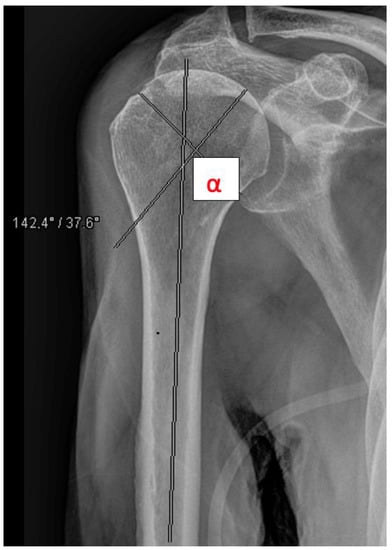

The head-shaft angle (HSA) was measured by a resident and a consultant radiologically preoperatively, postoperatively, and after 6 weeks in all fractures except A1 fractures (Figure 4). Primary outcome measures included secondary dislocation and surgical complications. Secondary outcome measures included function after 3 months, mortality, and discharge disposition. A one-year follow up to obtain information about the mortality and complications was performed by analyzing the electronic record of the patient. In the geriatric and partly immobilized collective, many patients were not seen as outpatients. In these cases, follow up was performed by phoning the patients.

Figure 4. Measurement of the head shaft angle (HAS, e.g., 14.2°).